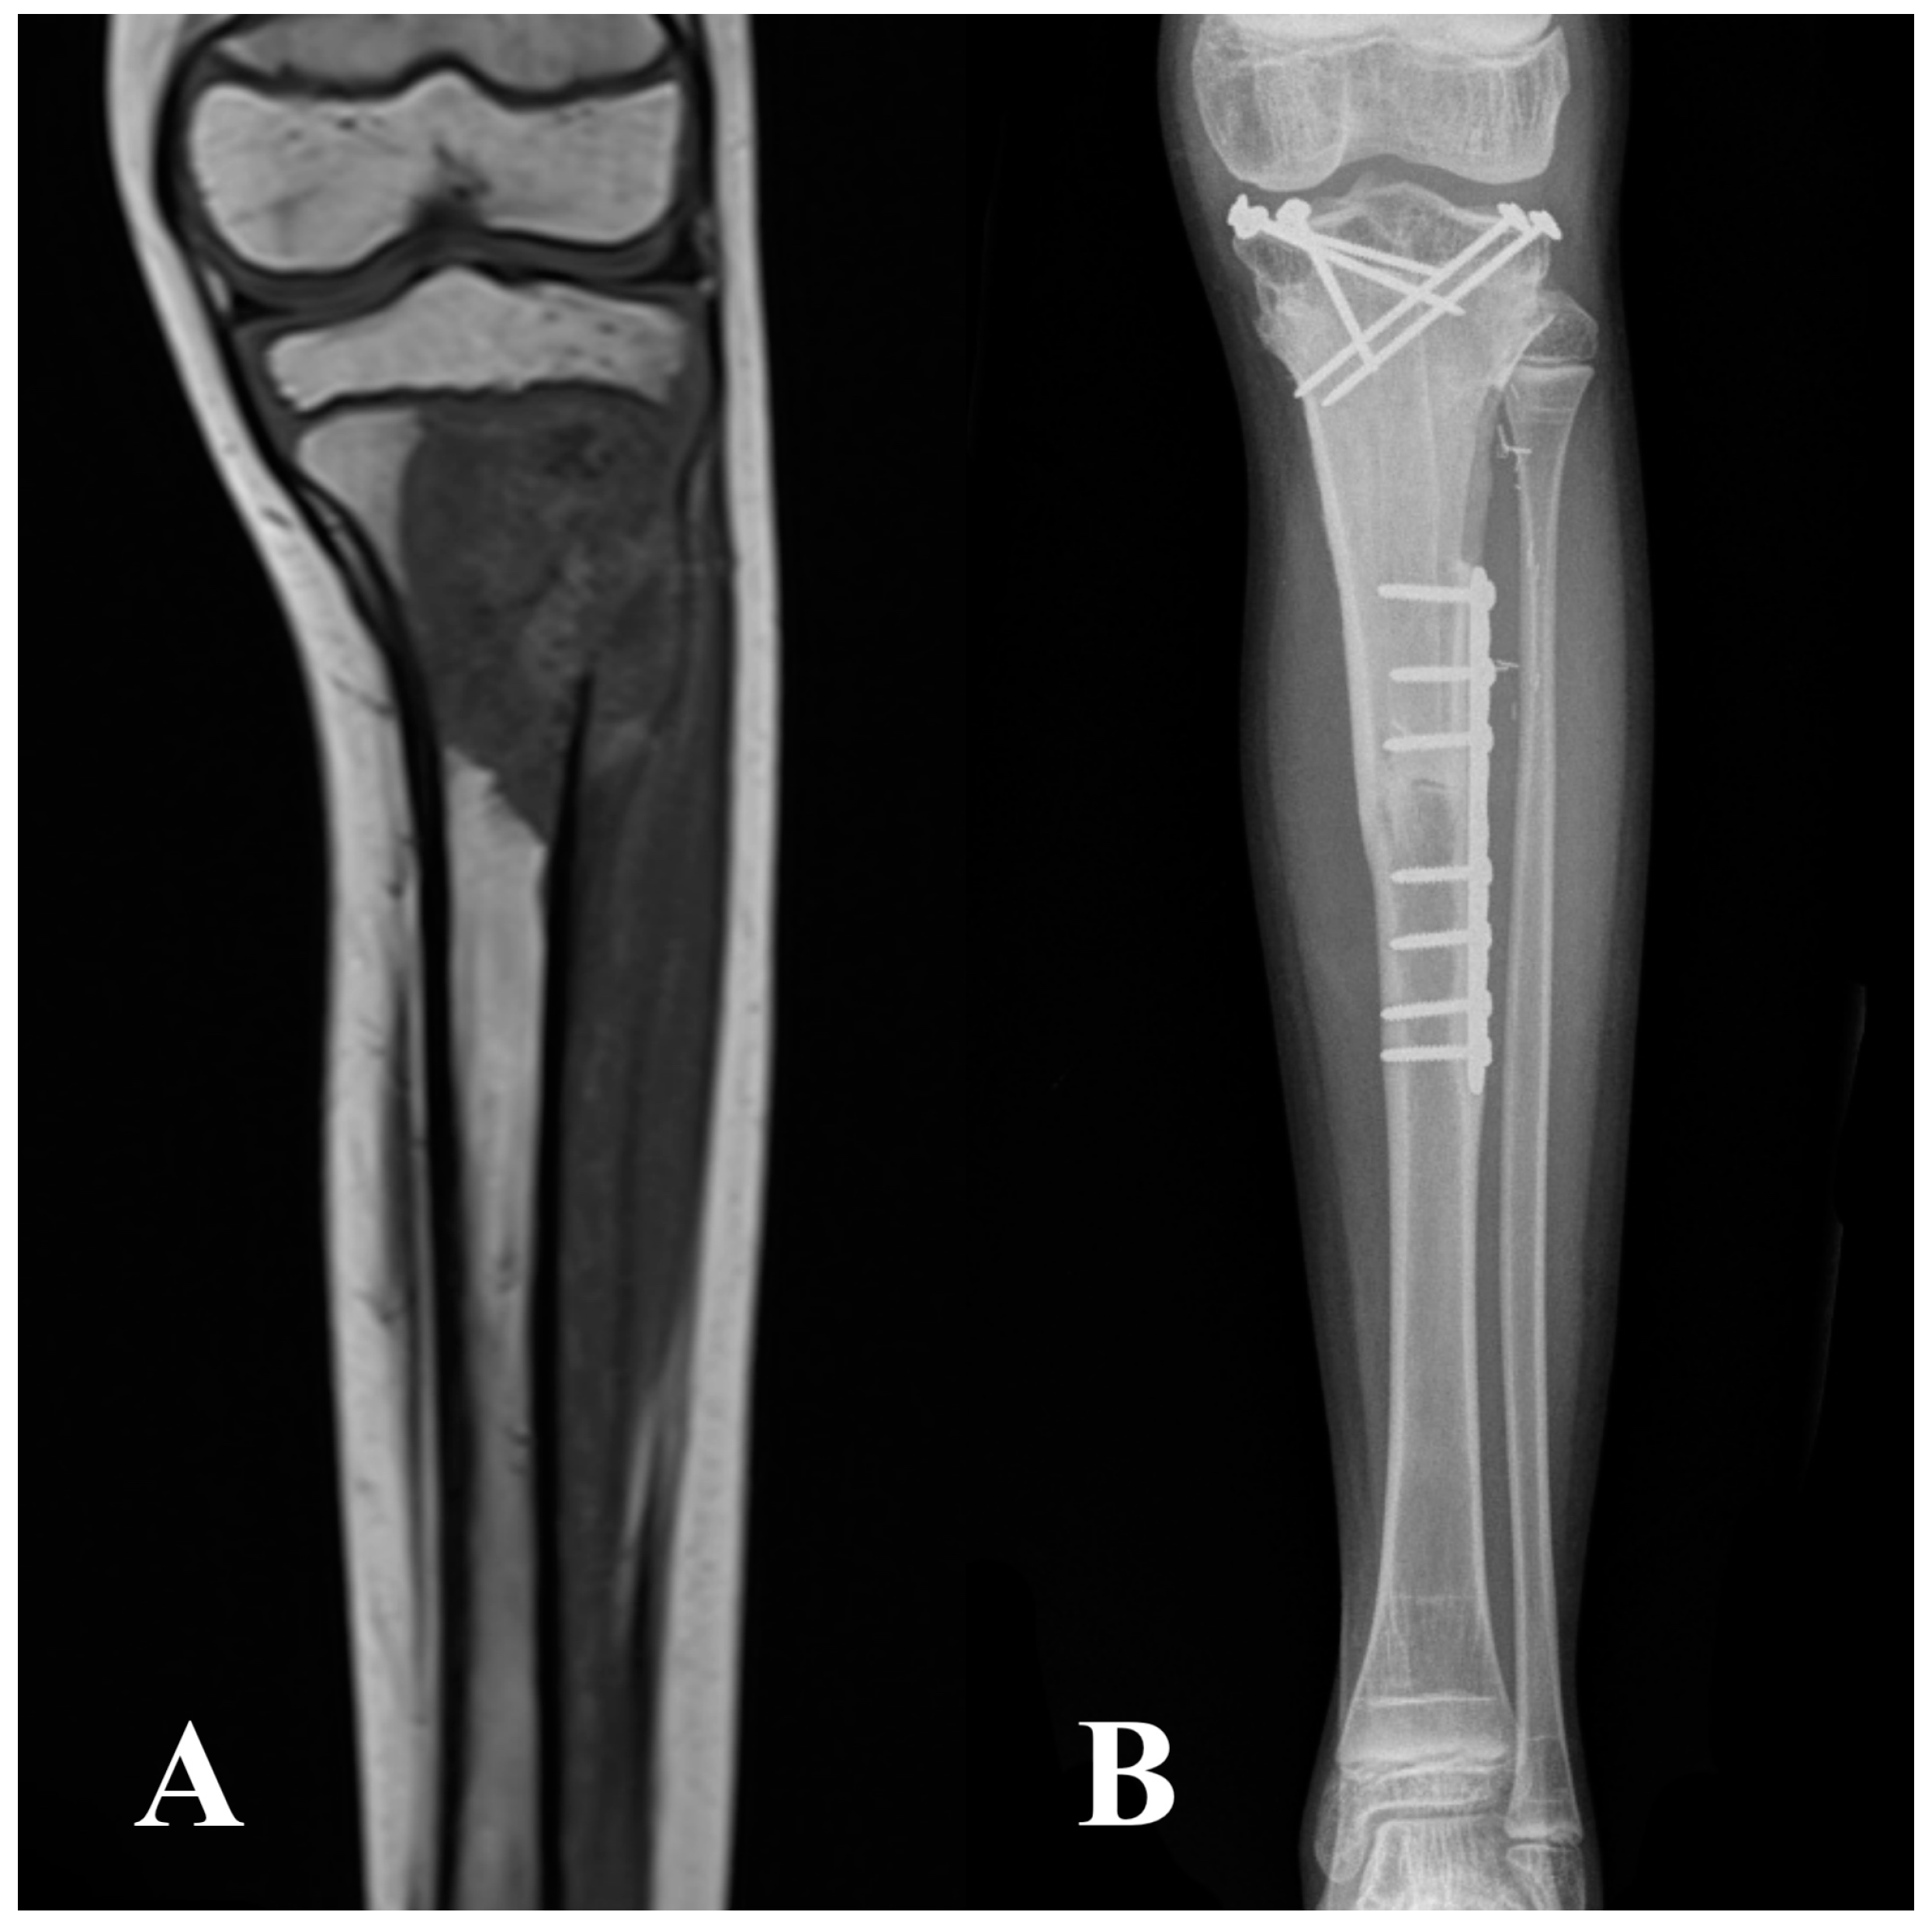

2.2. Surgical Technique, Aftercare, and Cancer Treatment

| Intercalary | 77 (10) | 58 (15) |

| Intraepiphyseal | 23 (3) | 42 (11) |

| Fixation method | ||

| Metaphyseal screws + diaphyseal plate | 15 (2) | 42 (11) |

| Only screws | 8 (1) | 12 (3) |